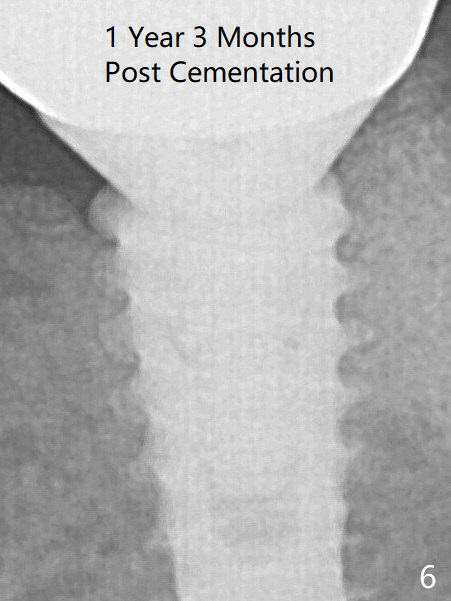

A provisional is fabricated 3 weeks postop.  The provisional and abutment are loose 4 months postop (Fig.5).  After retightening the abutment, impression is taken for final restoration.